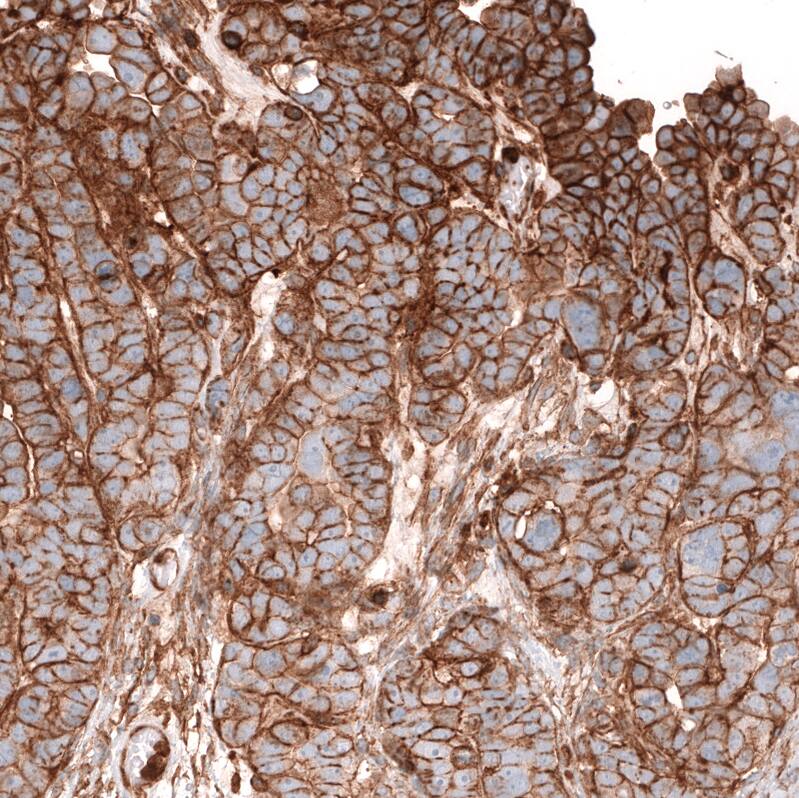

Staining of human ovarian cancer (low grade serous ovarian carcinoma) shows strong membranous positivity in tumor cells.